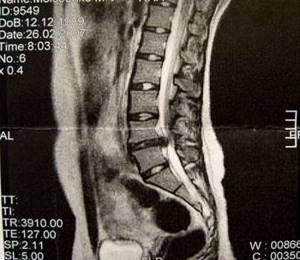

МРТ фото при секвестрированной грыже L5-S1

На снимке отображен крупный дефект, обусловленный значительным выпадением межпозвонкового диска.

На первом МРТ фото прослеживается крупная грыжа после хирургического лечения. На фоне патологии у человека формируется сильный стеноз спинного мозга. Выпадение межпозвонкового диска располагается в сегменте L5-S1. Патология осложняется небольшим секвестром.

На основании магнитно-резонансных томограмм удается установить подвижность небольшого фрагмента. После чтения результата размеры выпячивания – в дорсальном направлении (14,5 мм), краниально-каудальном (26,8 мм).